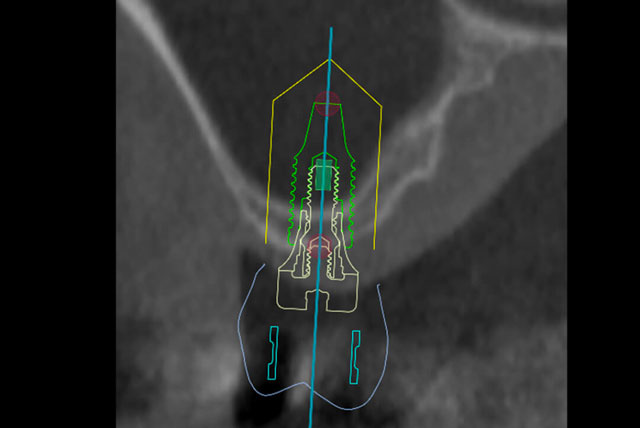

精密治療を安全に行うための高度なインプラントガイドを導入

インプラント治療では、人工の歯根を埋め込む位置がずれてしまうと、トラブルに繋がる可能性もあります。それを防ぐために、当院ではコンピューターシミュレーションソフトを利用したインプラント手術(ガイデッドサージェリー)を行っています。術前の診査・診断を基にしたシミュレーションを忠実に反映できる装置(サージカルガイド)を使用することで、寸分の狂いなく正しい角度、深度でインプラントを埋入することが可能です。専門医の技術と知識に加え、高度な医療機器を備えることで、患者さまにより安全で長持ちするインプラント治療をお届けできるよう努めています。